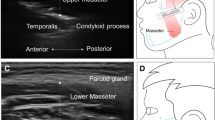

The aim of this study was to compare CSA values obtained by MRI and ultrasound for all submental muscles. However, the geniohyoid and mylohyoid muscle boundaries could not be visualized sufficiently to allow measurement of the CSA from MRI images (Fig. 1); hence, no comparison could be made for these muscles, although these measurements could be obtained from ultrasound images (Fig. 2). CSA measurements of the mylohyoid muscle were not possible using ultrasound images (Fig. 2), as the lateral borders of the muscle were not visible. Therefore, only calculation of one-dimensional (1D) thickness of the mylohyoid was possible from ultrasound images (Fig. 2). As the clarity of the mylohyoid muscle was not sufficient to measure 1D thickness using MRI images (Fig. 1), analysis was limited to comparison of the anterior belly of the digastric muscle.

CSA measurements of the geniohyoid muscle and thickness measurements of the mylohyoid muscle were not possible on MRI images due to poor border delineation (Figs. 1 and 2). These muscles could be differentiated and measured from ultrasonographic images, suggesting that there is a difference in the sensitivity of the two methods for demarcating these muscles. The acquisition of MRI images in this study required a longer duration of movement inhibition (3 min) than ultrasound image acquisition (0.3 s). As the submental muscles are activated during swallowing at least once every minute [28], it is likely that image clarity was compromised to a greater degree for MRI than for ultrasound. CSA measurements were taken from the muscle’s belly in both ultrasound and MRI images. As most movement occurs at the muscle’s belly, controlling movement is essential for CSA measurements from this location, which suggests that the advantage of rapid acquisition time of ultrasound is especially applicable in this case. The difference in signal generation between the two methods also may contribute to the superior image quality documented for ultrasound in this study. Because ultrasound uses the change in reflective properties of adjacent tissues, it may be more sensitive to the muscle borders in this confined space than MRI, which generates a signal based on proton density. In addition, because of scanning schedules, image acquisition duration, and limited funding for the acquisition of the MRI images, it was possible to scrutinize and repeat image acquisition if movement artifact was detected during only the ultrasound procedure.